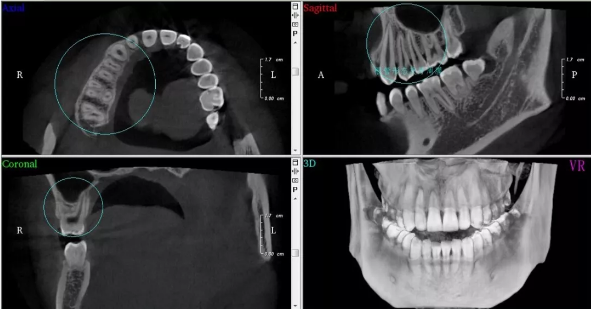

口腔ct(cbct)

图片尺寸620x408